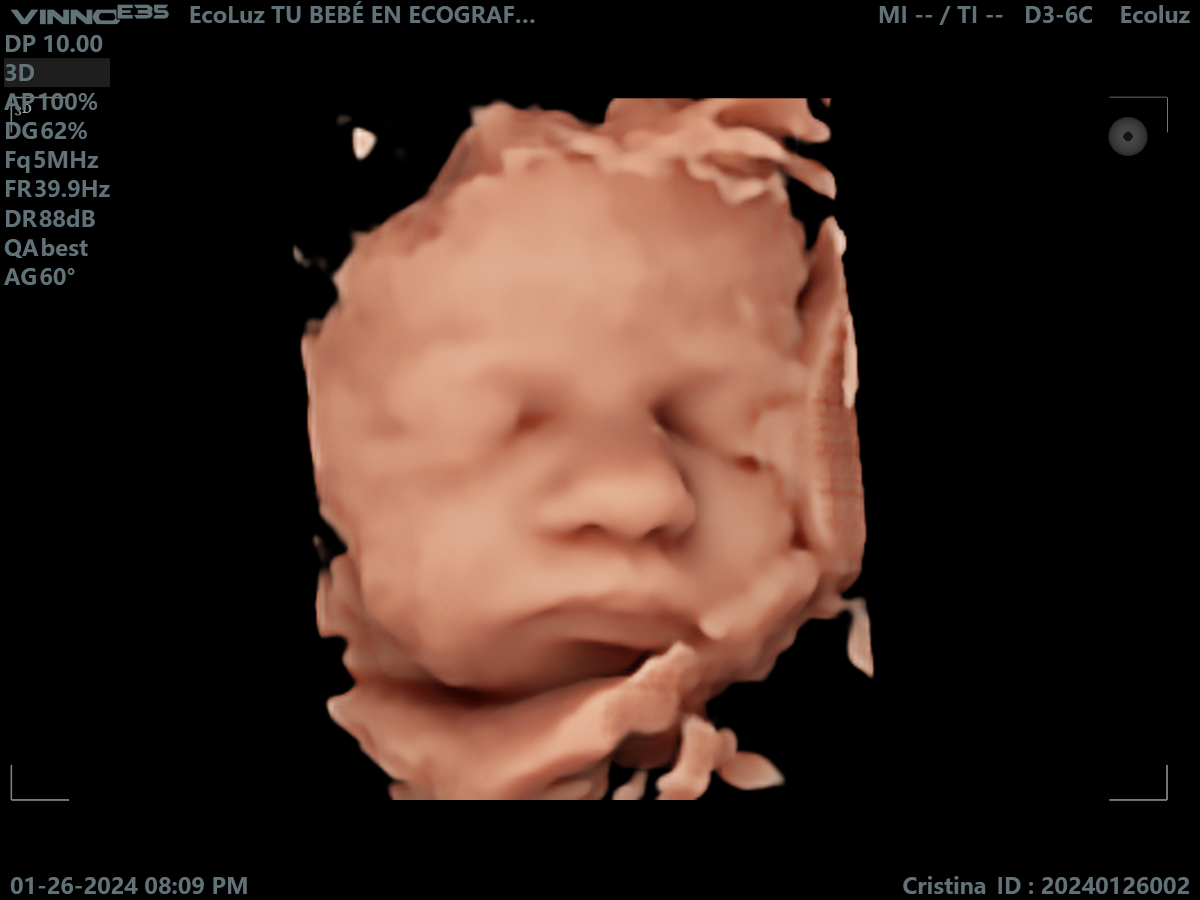

A las 30 semanas, tu bebé ya tiene una apariencia muy similar a la que tendrá al nacer. La eco 30 semanas permite disfrutar de imágenes claras, emotivas y llenas…

En esta etapa del embarazo, la eco 30 semanas muestra un bebé más grande y con menos espacio para moverse, lo que facilita ver su rostro más fijo en pantalla.…

Muchas familias consideran la ecografía de 30 semanas como una de las más impactantes visualmente. La definición del rostro y los detalles son sorprendentes. 💫 En EcoLuz 5D creamos un…

A las 30 semanas, el bebé ya tiene una expresión muy reconocible. La ecografía 30 semanas permite captar gestos únicos que emocionan a toda la familia.